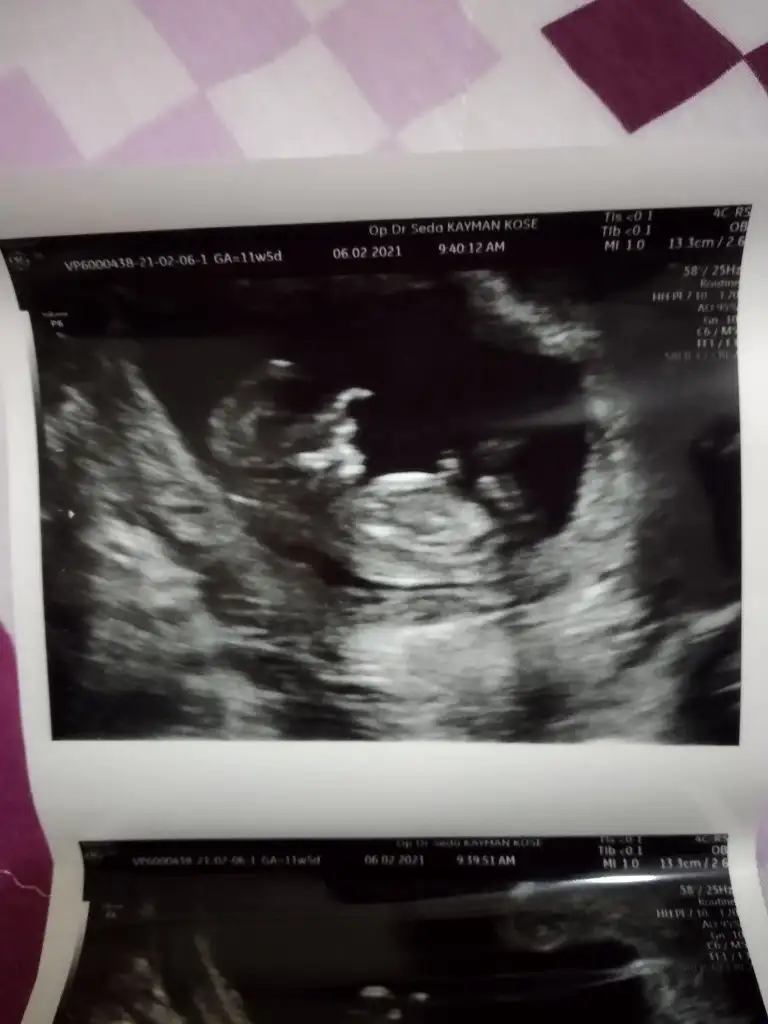

Buna göre erkek görünüyor ama en iyi 11 12 13 haftalar olmalıMerhabaIkra meyra , benim ultrason görüntülerime de bakabilir misiniz lütfen?

7+2 haftalık ve vajinal ultrason..

Eki Görüntüle 2777351 Eki Görüntüle 2777352

Merhaba bize de bir tahmininiz olur mu acabaBuna göre erkek görünüyor ama en iyi 11 12 13 haftalar olmalı